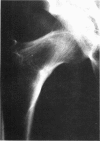

Follow-up studies have been performed in nine of 12 workers who were initially investigated in 1962. In six of the men exposures ranged from 28 to 45 years to cadmium sulfide dust and for shorter periods in the earlier years to cadmium oxide fume and dust. These six men had tubular proteinuria when first seen, and this has persisted in the five survivors. All six men had hypercalciuria, and two of them became recurrent stone formers. One man whose urinary calcium excretion later fell to a low level more recently developed vitamin D resistant osteomalacia. In addition, each of the six men had exhibited some, but not all, of a variety of biochemical abnormalities related to other proximal renal tubular defects, and the worker who developed osteomalacia had additional evidence of a distal tubular defect. The five survivors also have evidence of slowly progressive deterioration in glomerular function.

Images in this article